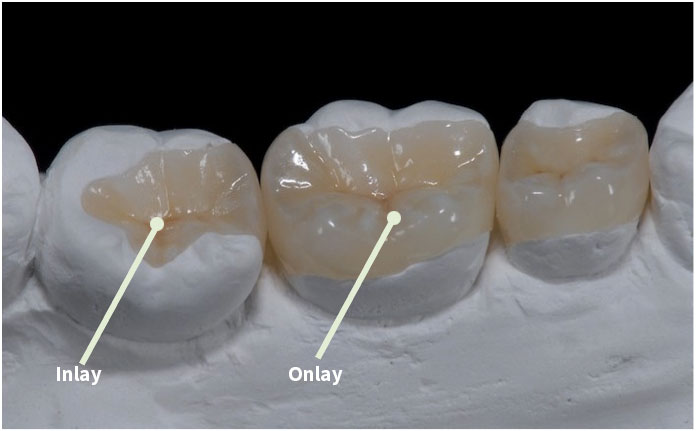

Vật Liệu Sứ: Trám răng bằng Inlay/Onlay vật liệu sứ nguyên khối cung cấp một giải pháp thẩm mỹ rất tốt và bền vững.